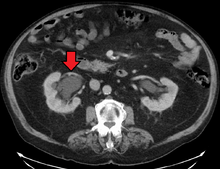

Imaging studies, such as an intravenous urogram (IVU), ultrasound, CT or MRI, are also important investigations in determining the presence and/ or cause of hydronephrosis. Whilst ultrasound allows for visualisation of the ureters and kidneys (and determine the presence of hydronephrosis and / or hydroureter), an IVU is useful for assessing the anatomical location of the obstruction. Antegrade or retrograde pyelography will show similar findings to an IVU but offer a therapeutic option as well. Real-time ultrasounds and color-flow Doppler tests in association with vascular resistance testing helps determine how a given obstruction is effecting urinary functionality in hydronephrotic patients.[12]

The choice of imaging depends on the clinical presentation (history, symptoms and examination findings). In the case of renal colic (one sided loin pain usually accompanied by a trace of blood in the urine) the initial investigation is usually a spiral or helical CT scan. This has the advantage of showing whether there is any obstruction of flow of urine causing hydronephrosis as well as demonstrating the function of the other kidney. Many stones are not visible on plain X-ray or IVU but 99% of stones are visible on CT and therefore CT is becoming a common choice of initial investigation. CT is not used however, when there is a reason to avoid radiation exposure, e.g. in pregnancy.